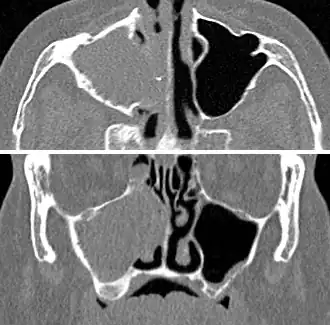

MRI image showing sinusitis. Edema and mucosal thickening appear in both maxillary sinuses. -